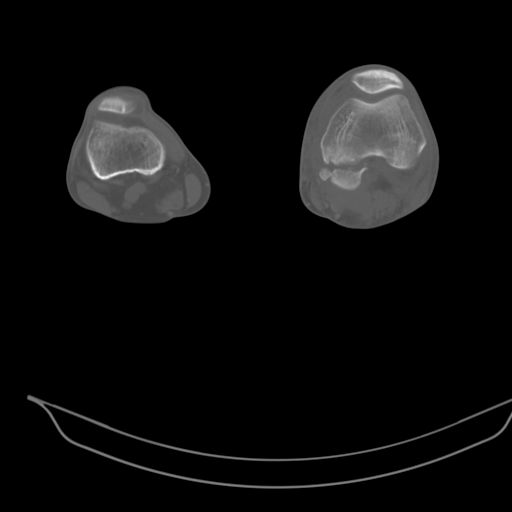

CT shows major bony fragments which are markedly rotated .With this amount of bony damage,you probably should attempt to get reasonably loooking knee with ORIF and thn if he needs a TKR due to pain a few years from now, then tleast you have something looking like a knee that you can replace rather than having to use revision knee for a primary TKR now. 4 weeks is not too long .what is the condition of soft tissues?

При внутрисуcтавных переломах трехмерные (3D) изображения, кроме красивого снимка, не дают полную информацию о состоянии отломков, самыми информативными являются корональные срезы на КТ и обычная длинная ренгенограмма конечности для сравнения оси конечности.

Фронтальные внутрисуставные переломы мыщельков бедра, так называемые Hoffa fracture, не частые, но встречающиеся переломы, в основном они связаны с травмой высокой энергией.

В зависимости от смещения рекомендуется сопоставление костных фрагментов с последующей жесткой фиксацией.

В вашем случае доступ будет медиальный, сопоставить развернутый медиальный мыщелок и фиксацию надо произвести в передне-заднем

направлении шурупами 4.5 мм в диаметре, углубив головку шурупов под хрящ, а поперечную фиксацию - межмыщелковыми шурупами. Желательно применить шурупы 6.3 мм в диаметре. Дополнительная Buttress technique пластина предотвратит перелом от скольжения.